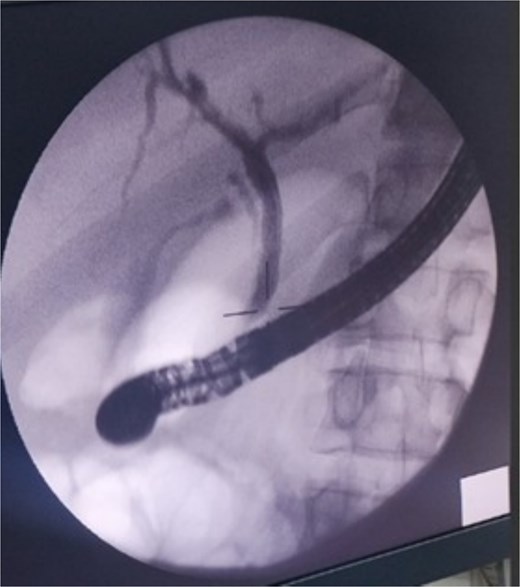

Around 6Â months later, the patient underwent a follow-up ERCP. The biliary system was intact, with no contrast leak seen, and the previous stent was removed without complications. The biliary fistula was successfully resolved.